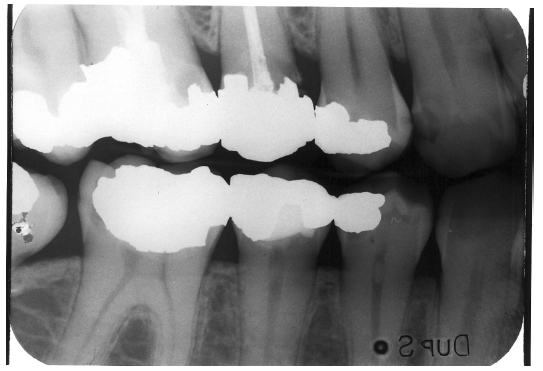

The junction of a restored tooth and the restorative material should always appear sharp and distinct, though there will be some qualitative differences for interposed radiolucent bases. Restorations that radiographically fail to extend to tooth preparation margins (open margins), those that extend beyond the preparation margins (overhangs), and those with inappropriate contours may be considered defective restorations. Such restorations are usually defective at the time they are inserted, though they may become defective as a result of fracture, attrition, abrasion or erosion.

Figure 1 is a molar bitewing radiographic image that discloses a defective abutment restoration on tooth #4. The restoration ends short leaving open margins.

Figure 1 - Defective Restoration; Abutment Tooth #4

Figure 1